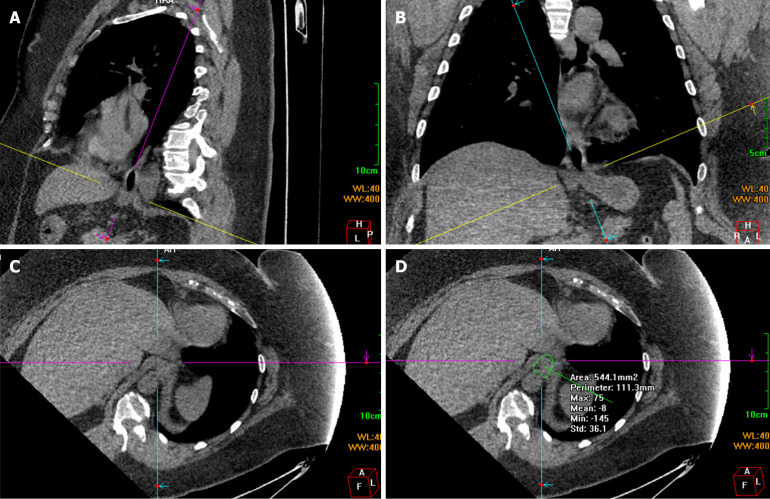

Methods: A total of 158 patients, aged 20-49 years, was analyzed from January 2020 to June 2024. The patients were classified into the no reflux esophagitis (RE) no HH group (HHG), RE group, and type I HHG. The transverse and sagittal diameters and cross-sectional area of the esophageal hiatus were measured using multiplanar reconstruction of the computed tomography images.

Results: Body mass index was positively correlated with area and transverse and sagittal diameters of the esophageal hiatus (r = 0.72, 0.69, and 0.54, respectively; P < 0.01). In the no RE no HHG and RE group, the esophageal hiatus size in the subgroup with obesity was greater than that in the non-obesity subgroup (area: 326.15 ± 78 mm2 vs 208.12 ± 64.44 mm2, transverse diameters: 15.97 ± 2.06 mm vs 13.37 ± 1.99 mm, sagittal diameters: 15.7 ± 2.08 mm vs 11.73 ± 2.08 mm; P < 0.01). Patients with obesity showed no significant differences in esophageal hiatus size with or without RE or HH.